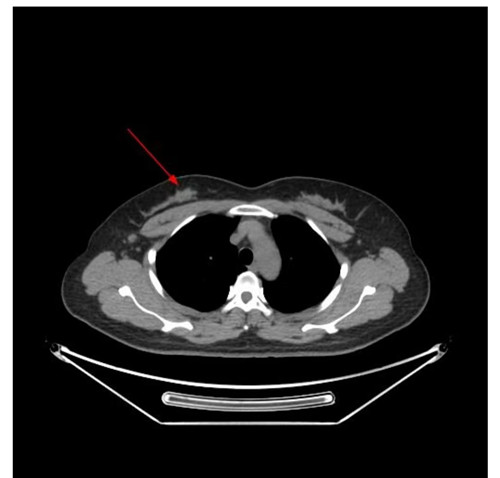

PETCT显示右侧乳腺内糖代谢明显增高的结节和腰椎的转移癌

问题来了,彭女士腰椎转移癌原发灶在哪里?是甲状腺癌吗?因关系后续治疗方案,在医生的建议下,彭女士到捷克论坛 PET影像中心进行PET/CT扫描。检查结果让人大吃一惊,彭女士的右侧乳腺有一个糖代谢明显增高的结节,大小为10mm,高度提示右侧乳腺癌。这下解开了腰椎转移癌的谜底,乳腺癌除腰椎骨转移外,同时发现右侧腋窝淋巴结和骨盆多骨的转移。目前,彭女士已经转入乳甲外科接受手术及进一步治疗。